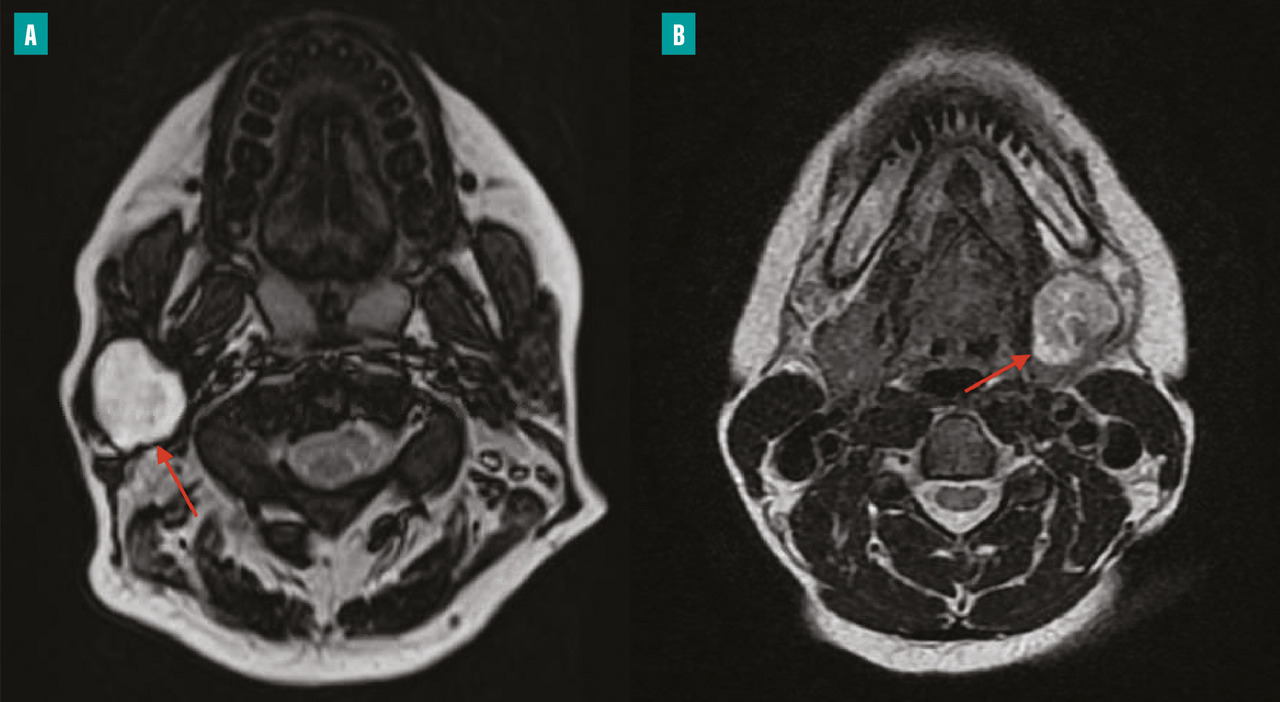

IRM, examen de choix

L’IRM constitue l’examen de choix dans l’exploration de la pathologie tumorale des glandes salivaires (fig. 2 ). Elle comprend des séquences T1, T2 et des séquences de diffusion et de perfusion après injection de gadolinium. Les séquences morphologiques recherchent des critères de malignité tels qu’une lésion mal limitée, envahissant les structures de proximité. Les séquences de perfusion permettent d’obtenir trois types de courbes : les courbes de type A sont évocatrices d’adénome pléomorphe ; les courbes de type B suggèrent une tumeur de Warthin ; les courbes de type C orientent vers une tumeur maligne. Les séquences de diffusion permettent aussi une orientation diagnostique par le calcul du ratio d’ADC (coefficient de diffusion apparent) : un rADC > 1,3 est en faveur d’un adénome pléomorphe ; un rADC < 1 est en faveur d’une tumeur maligne ou d’une tumeur de Warthin ; un rADC autour de 0,5 fait évoquer un lymphome.12 En couplant ces trois modalités, l’IRM permet de détecter une tumeur maligne avec une sensibilité de 86 % et une spécificité de 90 %.13